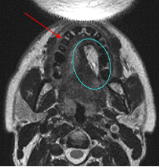

A radial forearm free flap replaced tissue removed in tongue cancer surgery

The flap appears white in the MRI because of its high fat content.

![]() | ![]() | ![]() |

| Sagittal | Coronal | Axial |